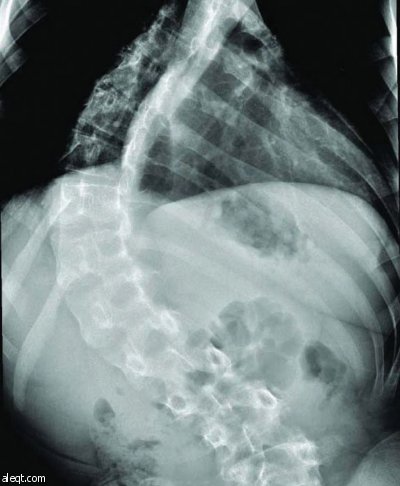

نجح فريق طبي في مستشفى الملك خالد الجامعي في جامعة الملك سعود في إنهاء معاناة مريض في الثالثة عشرة من عمره أصيب بالشلل نتيجة انحراف شديد في العمود الفقري (الجنف) وتأخر في العلاج حتى وصلت نسبة الانحناء إلى (140درجة).

وتم تنويم المريض بشكل عاجل وأجريت له عملية جراحية لإزالة الضغط عن الحبل الشوكي وتم تقويم الظهر من الخلف حيث تمكن المريض من المشي والعودة لممارسة حياته الطبيعية بعد العملية مباشرة ولله الحمد.